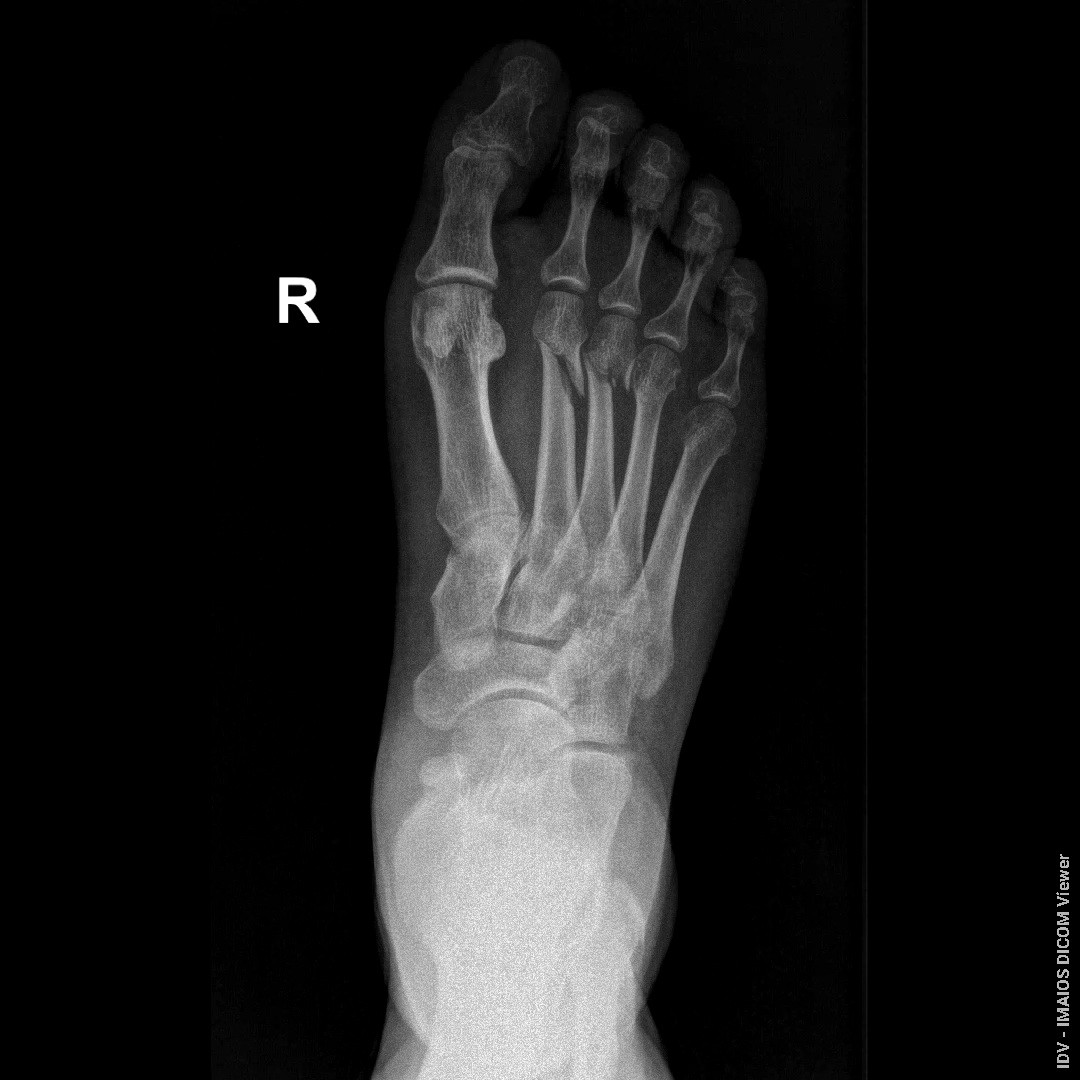

Здравствуйте, доктор, переломы были 23.06.2025, прошло уже почти 7 недель, возможно ли судя по снимкам образования ложных суставов, если будет срастаться плохо? прикрепляю последние снимки от 08.08.2025

Здравствуйте. Ложный сустав за 7 недель не формируется, на снимках есть признаки сращения, но перелом ещё не полностью зажил, поэтому нужен щадящий режим и контроль у травматолога.

Андрей Павлович, Большое Спасибо Вам за ответ! Я понял, что за 7 недель ложнвй сустав не формируется, но если переломы так до конца и не срастутся, возможно ли формирование ложных суставов? На приложеных снимках есть два первичных снимка от 23.06.2025 и один с5имос вчерашний, от 08.08.2025

Да, при отсутствии сращения со временем возможно формирование ложного сустава, поэтому важно наблюдаться у травматолога и контролировать процесс заживления.